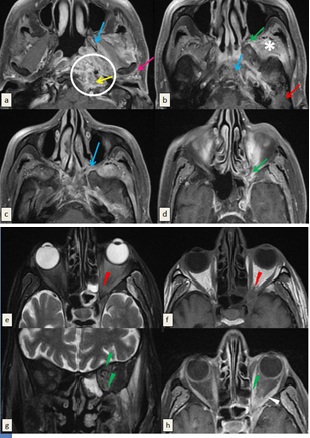

The infection extended to the pterygopalatine fossa medially. Then, it reached the left orbit via the inferior orbital fissure causing proptosis, intraconal fat stranding and thickening, edema and significant enhancement of the orbital muscles. No enhancement of optic nerve was detected (Figure 1).

Figure 1: Magnetic resonance imaging (MRI) (3 Tesla) of the skull base performed in T1-weighted sequence before (f) and after saturation of the fat signal and injection of gadolinium (a, b, c, d, h) and T2-weighted sequence after suppression of the fat signal (e, g) ruling out necrotizing otitis externa. The wall of the left external auditory canal is thickened and enhanced after injection of gadolinium (White arrow) associated with inflammatory filling of mastoid cells and middle ear cavities (Red arrow). T1-weighted images show cortical irregularities and enhancement of the bone marrow of the pterygoid process and the clivus related to the osteomylelitis of skull base (Blue arrows).There is synovitis of the left temporomandibular joint attested by the inflammatory changes of periarticular soft tissues(pink arrow). Signal anomalies and enhancement after contrast spread to the ipsilateral infratemporal fossa (Asterix) and to the parapharyngeal, vascular and retropharyngeal spaces (Circle) with several small contiguous collections of parpharyngeal space forming an inflammatory pseudo-mass bulging into the nasopharynx. Extension to the vascular space is accompanied by thrombosis of the ipsilateral jugular vein (Yellow arrow). Demonstration of an obliteration of the fat of the pterygopalatine fossa and the inferior orbital fissure (Green arrows) becoming hypointense in T1-weighted images, hyperintense in T2-weighted images and enhancing after contrast. The intra-orbital extension is attested by the proptosis, intraconal fat stranding (Red arrowhead) and by thickening, edema and significant enhancement of the orbital muscles (Green arrow head). No enhancement of optic nerve in retro-bulbar or intraorbital region was detected.